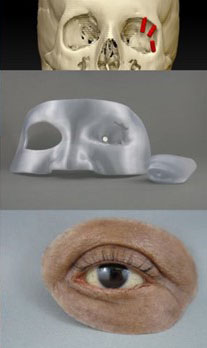

Histology is the study of the different tissues of the human body at the microscopic level. Understanding the structures of the human body from the macroscopic (Anatomy) to the microscopic (Histology) levels will aid in anaplastology treatment planning.

Cancer, birth differences and traumatic incidences, the most common reasons patients seek the care of clinical anaplastologists, will impact different tissues in the body: bone, skin, muscle. Having a microscopic understanding of these tissues could influence patient care.